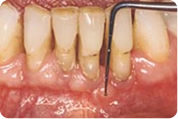

Kod ambulantnog liječenja se nakon određivanja stupnja upale ( kontrola plaka, krvarenja i mjerenja dubine džepova ) odstranjuju tvrde i meke naslage sa zubi ( čišćenje kamenca ); džepovi se odstranjuju kirurškim zahvatom ( uklanjanjem tkiva ili sredstvima koja pospješuju regeneraciju tkiva ). Također je potrebno sanirati zube i izraditi protetski nadomjestak kako bi se žvačni pritisak ravnomjerno rasporedio. Potrebne su redovite kontrole svakih 3-6 mjeseci.